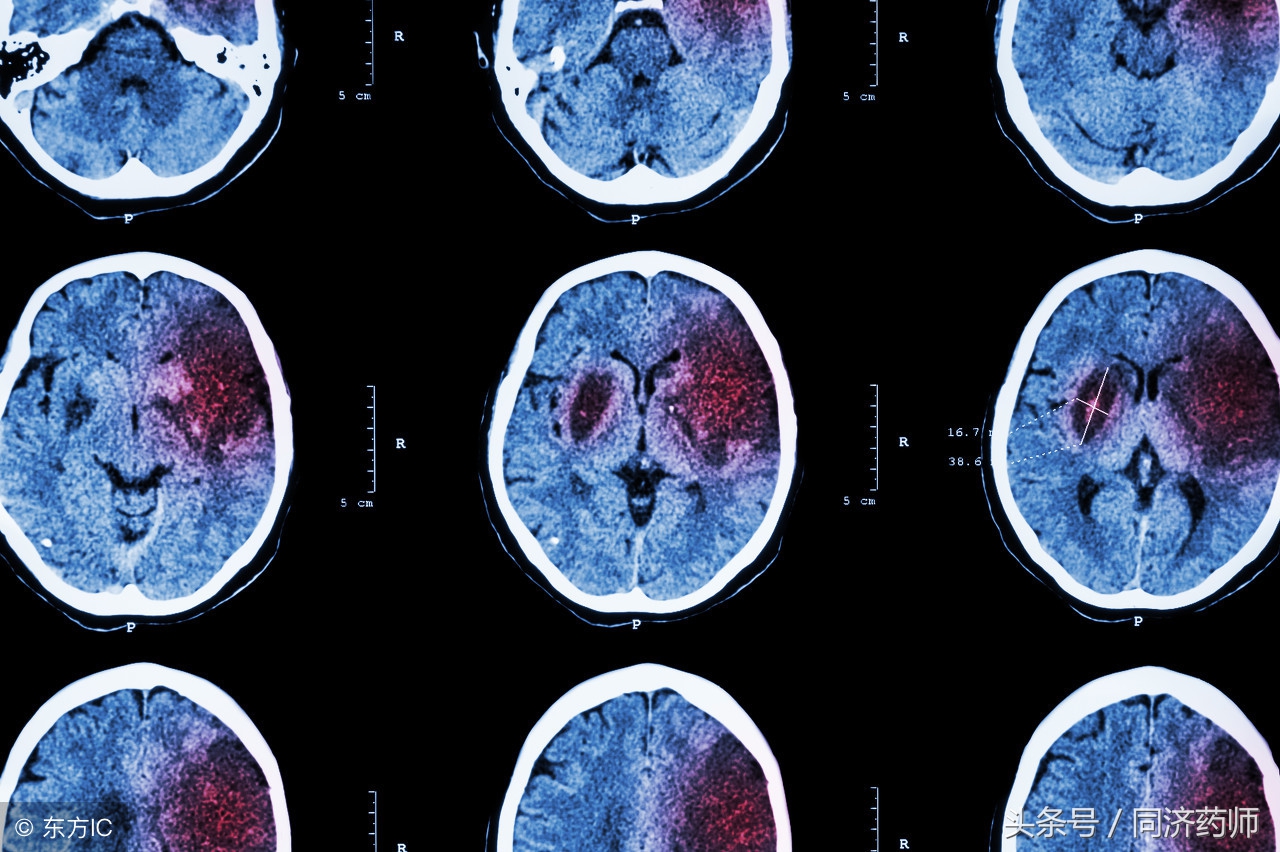

脑中风是一组以脑部缺血及出血性损伤症状为主要临床表现的疾病,又称脑卒中或脑血管意外,主要分为出血性脑中风(脑出血或蛛网膜下腔出血)和缺血性脑中风(脑梗塞、脑血栓形成)两大类,以脑梗塞最为常见。

由于其具有发病率高、死亡率高、致残率高、复发率高以及并发症多的特点,医学界把它同冠心病、癌症并列为威胁人类健康的三大慢性疾病之一。